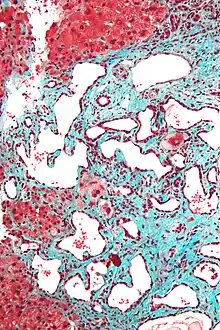

Micrograph of a bile duct hamartoma. Trichrome stain. Intermediate magnification

Micrograph of a bile duct hamartoma. Trichrome stain, high magnification

Low magnification micrograph of a bile duct hamartoma. Trichrome stain.